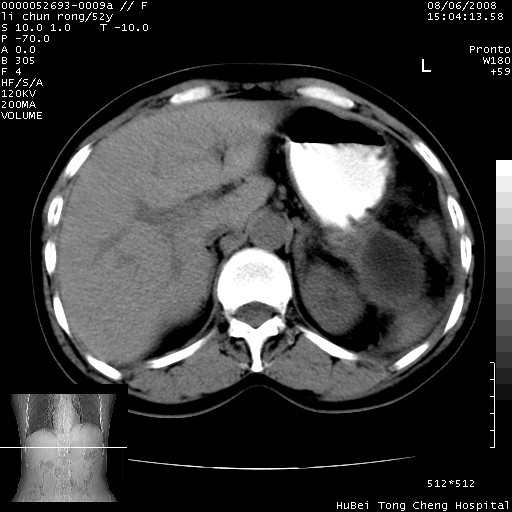

以下是引用云翔在2008-8-7 6:20:00的发言:[br]胰尾部囊性病变,考虑假囊肿,结合实验室检查疾病史

以下是引用zjzjr在2008-8-7 8:38:00的发言:[br]支持胰腺炎伴假囊肿形成,左肾小囊肿.少量腹水.

以下是引用随光逐影在2008-8-7 9:12:00的发言:[br]1)考虑胰腺炎伴假性囊肿形成可能性大;胰腺囊腺瘤待排。2)左肾小囊肿。3)少量腹水。